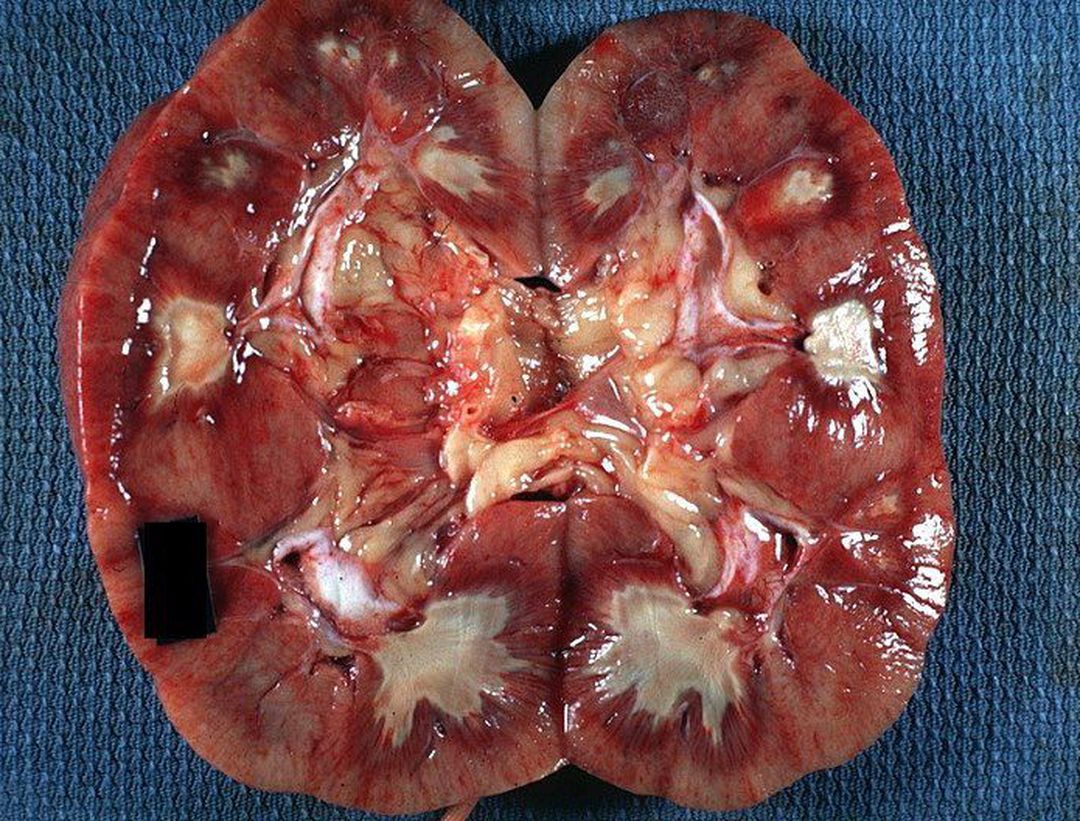

Kidney cross section showing renal papillary necrosis! The pale white areas involving some or all of many renal papillae are areas of ischemic papillary necrosis. This is an uncommon but severe complication of acute pyelonephritis, particularly in persons with diabetes mellitus. Papillary necrosis may also accompany analgesic nephropathy, sickle cell disease, and renal transplant rejection. The condition can lead to secondary infection of desquamated necrotic foci, deposition of calculi, and/or separation and eventual sloughing of papillae, with impending acute urinary tract obstruction. Multiple sloughed papillae can obstruct their respective calyces or can congregate and embolize to more distal sites such as the ureteropelvic junction, ureter, and ureterovesical junction. There is no definitive treatment. Underlying cause should be identified and the offending agent stopped.